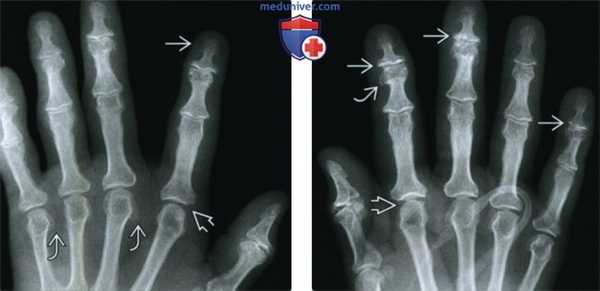

(Слева) Рентгенография кисти в ЗП проекции: визуализируются увеличенные, лопатовидные головки фаланг и расширенная суставная полость II пястно-фалангового сустава (ПФС). В головках пястных костей имеются клювовидные остеофиты. Эти признаки появляются в результате стимуляции образования новой костной и хрящевой ткани.

(Справа) Рентгенография кисти в ЗП проекции: определяется расширение полости ПФС и остеофитоподобные выросты на суставных поверхностях - типичные признаки акромегалии. Имеются дегенеративные изменения в ДМФ суставах.